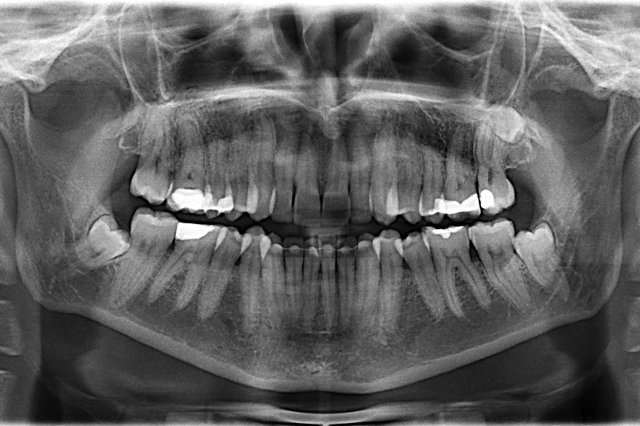

Tiefe Karies wegen eines benachbarten Weisheitszahnes

Tiefe Karies wegen eines benachbarten Weisheitszahnes ...

Composit-Füllung by CLINICDENT ✓

Tiefe Karies im oberen Weisheitszahn